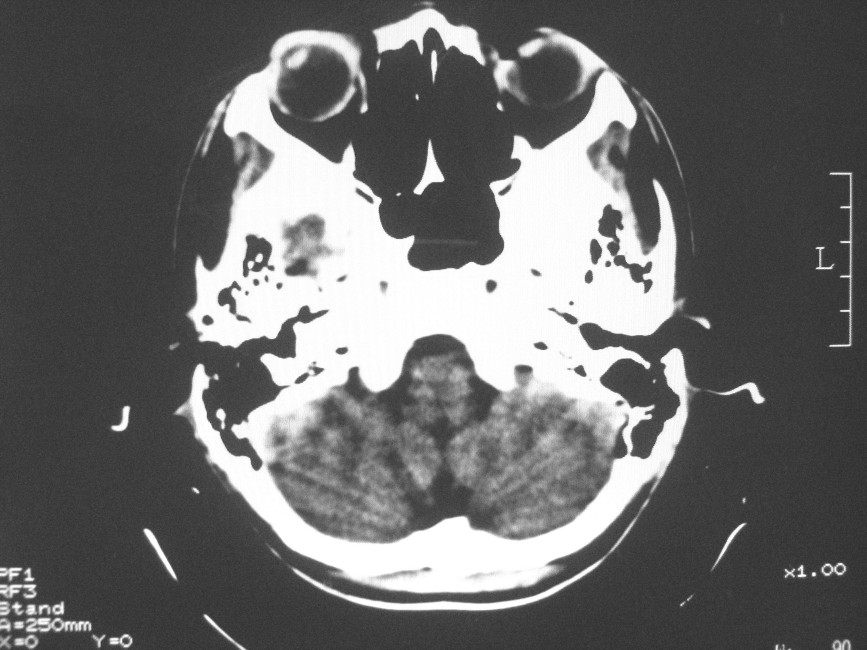

以下是引用zzyy在2008-6-16 10:13:00的发言:[br]两侧脑白质呈对称性密度减低,病儿有发热及脑膜刺激征。考虑急性病毒性脑炎。